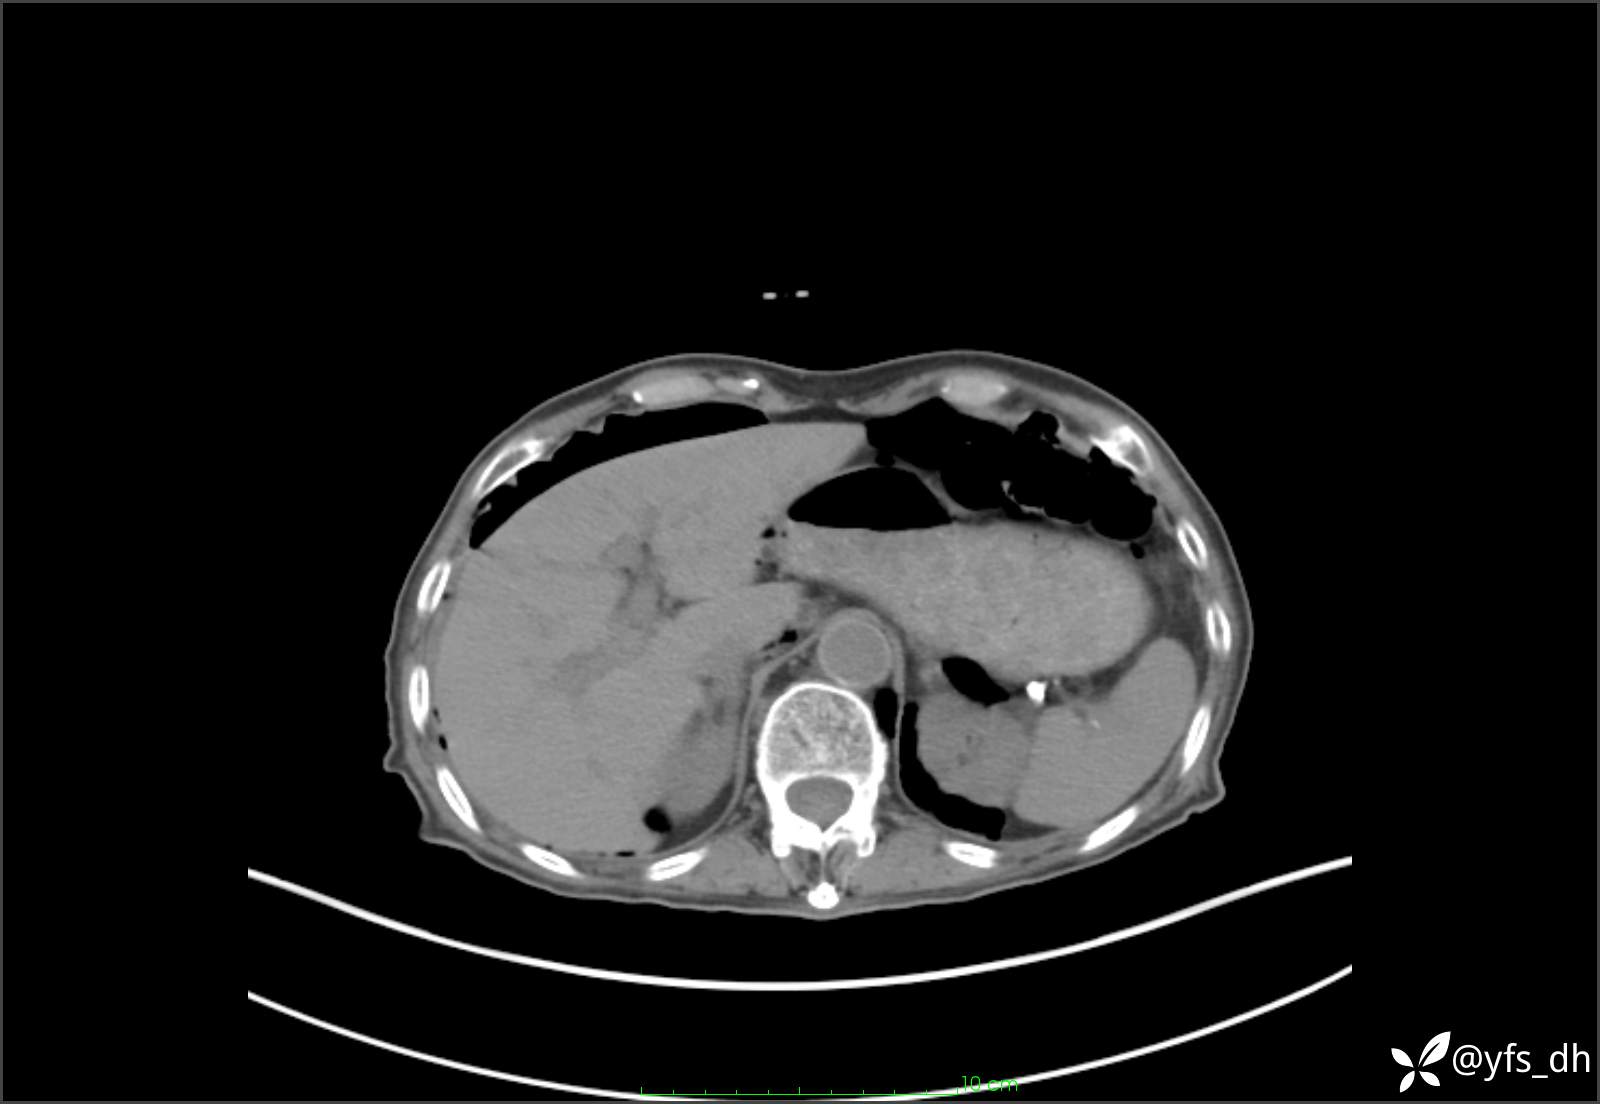

1.简要病史:患者4天前突发上腹部疼痛不适,但可以忍受。3小时前饭后突然加重,不能忍受后就诊。

2.简要手术记录:术中见腹盆腔大量肠液及粪便,乙状结肠中下段见一约3cm的破口。